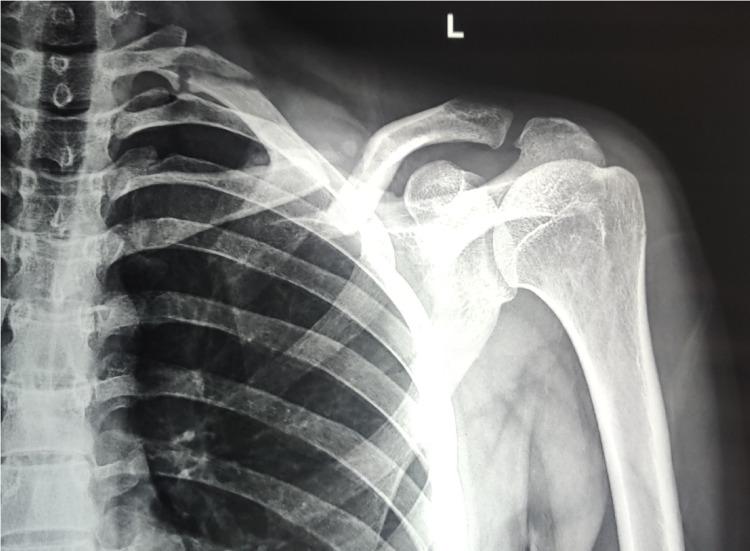

Introduction Fracture of the clavicle bone is a very common injury owing to its subcutaneous location. Controversy exists about the optimal treatment of midshaft clavicle fractures in the presence of significant displacement and comminution of the fracture. Traditionally, non-surgical management was considered the first treatment option for most clavicle fractures. However, recent evidence shows that the non-surgical option causes more complications than previously reported. The purpose of this study was to compare the clinical and radiological outcomes of conservative treatment and surgical treatment for midshaft clavicle fractures. Materials and methods A total of 45 patients meeting the inclusion criteria were included in this randomized study. The patients were allocated to two groups: conservative and operative on an alternate basis. Patients in the conservative group were managed with figure-of-eight bandage, whereas patients in the operative group were treated surgically by plate fixation. Primary outcome was recorded at six weeks, three months, six months, and 12 months follow-up using the Disabilities of the Arm, Shoulder, and Hand (DASH) and American Shoulder and Elbow Surgeons (ASES) scores. We also assessed patient's satisfaction after the treatment, fracture union, and complication rates among the study cohort. Results The ASES scores were significantly better in the operative group at three months and six months follow-up; however, at 12 months follow-up, there was no significant difference in the score between the groups. Although not statistically significant, the DASH score was better in the operative group than in the conservative group at all the follow-ups. This study showed that the time to union was lesser, rate of non-union was lower, and return to work was faster on the operative group. The mean satisfaction score in the operative and conservative groups was 4.16±0.76 and 4.05±1.24, respectively (p = 0.76). Conclusion This study suggests that open reduction and internal fixation with plate reduced the incidence of mal-union and non-union; however, surgical treatment showed no significant difference in the functional outcome as compared to conservative treatment.

引言 锁骨骨折因其位于皮下,是一种非常常见的损伤。对于存在明显移位和粉碎的中段锁骨骨折的最佳治疗方法存在争议。传统上,非手术治疗被认为是大多数锁骨骨折的首选治疗方法。然而,最近的证据表明,非手术治疗导致的并发症比以前报道的更多。本研究的目的是比较中段锁骨骨折保守治疗和手术治疗的临床和影像学结果。